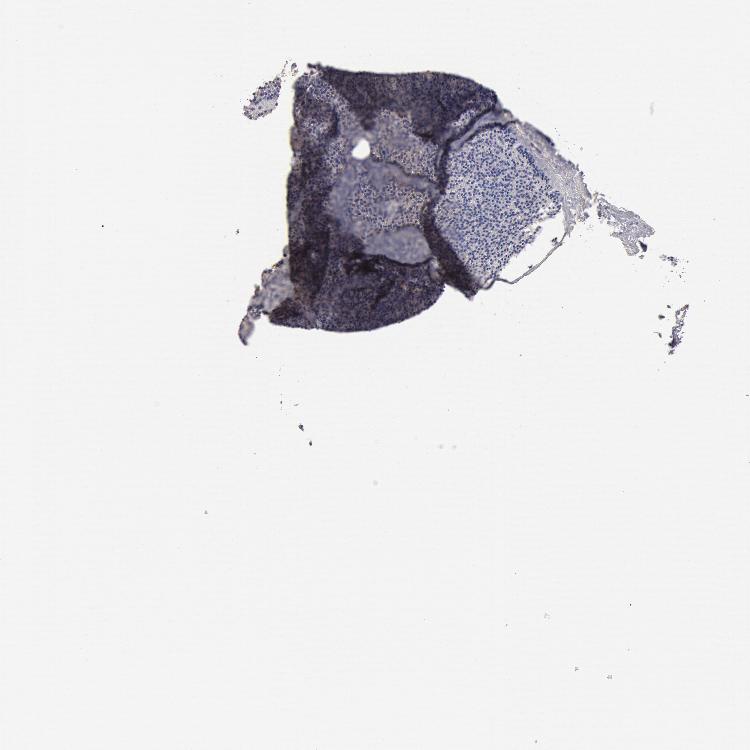

PARATHYROID GLAND - Antibody stainingi

Antibody staining in the annotated cell types in the current human tissue is reported as not detected, low, medium, or high, based on conventional immunohistochemistry profiling in selected tissues. This score is based on the combination of the staining intensity and fraction of stained cells.

Each image is clickable and will lead to virtual microscopy that enables deeper exploration of all samples and also displays staining intensity scores, fraction scores and subcellular localization as well as patient and tissue information for each sample.

Antibody HPA001205

Glandular cells Not detected